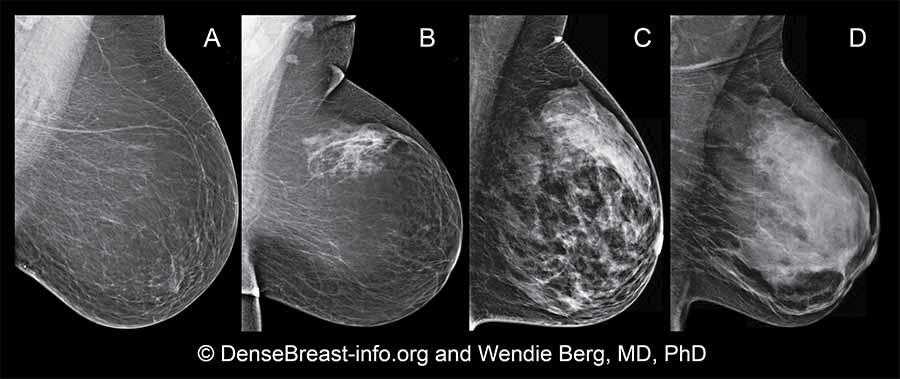

La mamografía es un estudio que utiliza radiación con el fin de identificar tejido mamario con anomalías.

Para realizarse, la persona se coloca frente a una máquina llamada mamógrafo para colocar una de los senos en una plataforma firme, posteriormente, se ejecuta una compresión entre dos placas con el propósito de analizar desde el pezón hasta el músculo pectoral.

A la hora de que se comprime el tejido, se explora desde distintos ángulos cada seno con una dosis pequeña de radiación.

El Instituto Nacional del Cáncer de los Institutos Nacionales de la Salud (NIH) especifica que los falsos positivos son más comunes en grupos de mujeres jóvenes, personas con mamas densas, quienes se hayan realizado biopsias previas y/o cuentan con antecedentes familiares de cáncer de mama.